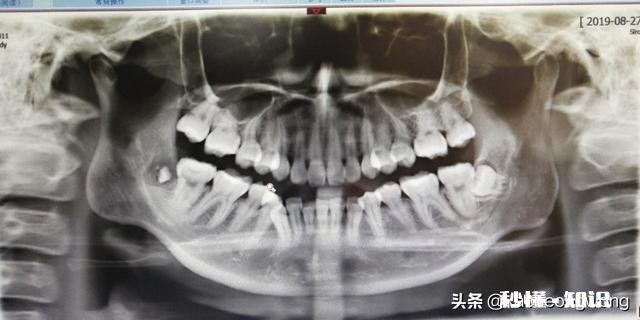

【智齿离神经多远】你看到这两个图右下角部位是患者左侧的智齿,这就距离神经管比较近,但具体是多少就要拍CT,因为这个全景X片是把颌骨曲面变成平面,所以会有重叠错位,你看到神经管在牙根之间其实很可能并没有,具体还是得看CT 。